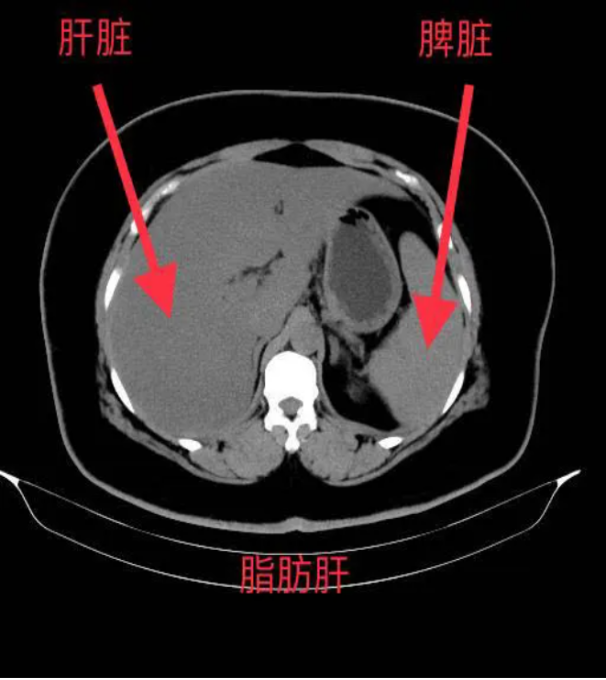

*肝臟密度降低:脂肪的CT值低于正常肝組織,因此脂肪肝在CT圖像上表現(xiàn)為肝臟密度普遍降低,與脾臟密度相比更加明顯。

*肝內(nèi)血管模糊:由于脂肪的堆積,肝內(nèi)血管在CT圖像上會(huì)變得模糊不清,甚至消失。

*肝脾CT值比值:正常情況下,肝臟CT值高于脾臟,而脂肪肝患者的肝脾CT值比值會(huì)降低,甚至出現(xiàn)反轉(zhuǎn)。